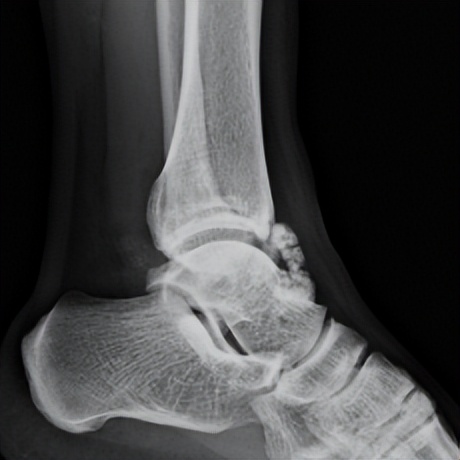

林先生来到省二医后,何河北医生为其进行了详细查体,检查后确诊为踝关节不稳+滑膜软骨瘤

何河北制定了详细的手术方案,为患者开展踝关节镜下滑膜软骨瘤取出术+距腓前韧带重建术。他从患者踝关节中取出32颗“珍珠”(关节游离体),然后进行踝关节外侧韧带重建。

▲术中取出31颗滑膜软骨瘤。

▲术后CT显示滑膜软骨瘤完全取出,韧带重建良好